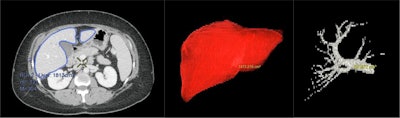

3D color-enhanced volume rendering was performed using the CT arterial and venous phase images. The images were imported in to GE AW workstation, and quantitative volumetric assessment was performed using the automatic hepatic VCAR tool with manual edits when needed. The hepatic artery, hepatic vein, and portal vein were extracted manually based on Hounsfield unit thresholds and were colored individually. Liver lobes were segmented using the virtual scalpel, and color enhancement was applied.

Overall, color enhancement could only be applied with 3D VR imaging and not MIP imaging. Volume calculation and isolation of liver segments were also possible with 3D VR but not MIP imaging. Image rotation in the superior to inferior, the anterior to posterior, and the lateral view was achieved with both modalities. Vessel delineation was better visualized with 3D VR imaging. The clarity of individual small vessels was suitable with both modalities. The overall performance indicates that 3D VR is the superior methodology to delineate the anatomical features, compared with the MIP.